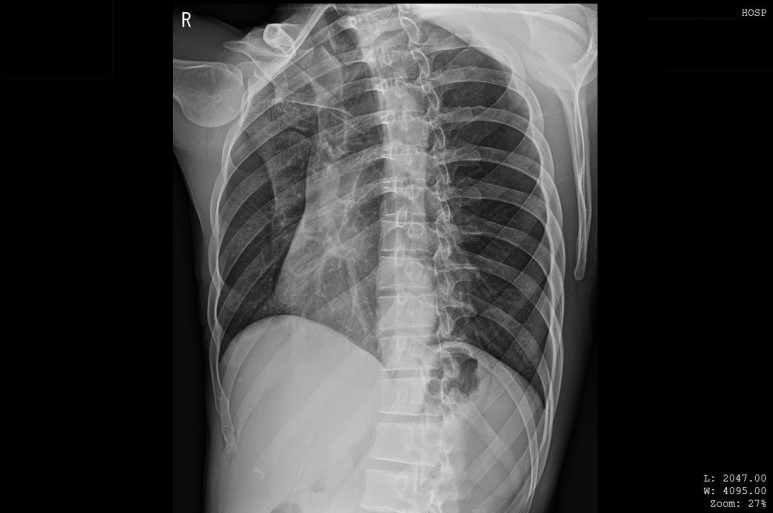

실제 늑골 골절 환자분이나 X-ray에서 골절선을 발견하지 못함

단순 방사선 검사에서

발견하지 못한 골절을

근육통, 염좌, 담결림으로 착각해서